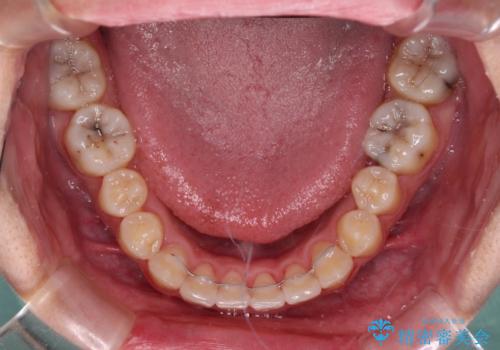

- 八重歯と叢生を気にして来院された患者様です。

上下の前歯が非接触であり、叢生や八重歯が顕著であったため、上顎左右第一小臼歯2本を抜歯して排列することとしました。

抜歯により移動量が多くなるため、ワイヤーや補助装置を活用し、その後インビザラインによる矯正治療を行うこととしました。

元々奥歯に負担のかかる咬み合わせですり減っていたため、仕上がった歯並びでも奥歯が咬んでいないように見えましたが、実際にはしっかりと咬合しており、患者様本人も咬んだ感触に違和感はないとのことでした。